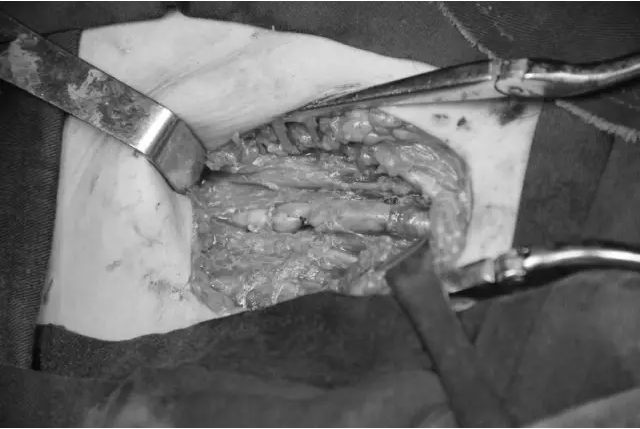

因各医保都处于年终结算期间,值班医生安乾积极帮助患者沟通医保转诊事宜,同时以最短的时间完成术前检查。血管外科崔文军副主任医师也在第一时间赶到医院,因同时两名患者需要急诊手术,又紧急通知夜班医生王颖主治医师赶到医院,协助完成第二名患者的信息采集和术前检查的完善。很快两名患者的病情都得以明确:来自濮阳的患者是外伤导致右侧股动脉损伤,当地医院无手术条件,仅予以简单缝合后予以止血钳钳夹(见图1),下肢皮温冰凉,末梢循环差,濒临坏死。来自驻马店的患者为急性下肢动脉栓塞,CTA提示腹主动脉下段及右侧髂总动脉血栓形成,血栓脱落后导致膝下动脉全部闭塞(见图2),右足皮温凉,皮色紫绀,趾端已出现坏死(见图3)。明确病情后,崔文军副主任医师及时向郑州大学五附院副院长、血管外科首席专家王兵教授汇报。王兵教授指示:手术指征明确,手术需争分夺秒!

接到通知的手术室、麻醉科人员早已到位,入院后不到1个小时,来自濮阳的患者已进入手术室,王兵教授与此同时也赶到手术室,手术在王兵教授带领下,由崔文军副主任医师、与安乾主治医师及吴斐住院医师协助共同完成。术中自股浅动脉取出大量新鲜血栓(见图4),因动脉毁损严重,无法直接缝合,取患者自体静脉予以重建(见图5),术毕患者右下肢皮温皮色即恢复正常。此时王颖主治医师也已完成第二个患者的术前准备,没有丝毫耽搁,原班手术人员滴水未尽,又紧张的投入到第二台手术中。手术过程同样顺利,经右股动脉切开后自腹主动脉及髂动脉取出大量新鲜血栓,同时完成膝下动脉的取栓(见图6),术后患者下肢的温度及颜色同样明显改善。